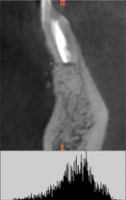

Пациент М, 22 года обратился на прием с жалобами на ноющую боли, чувство распирания в зубе 4.1.

Основываясь на данных рентгенологического исследования был поставлен диагноз «хронический апикальный периодонтит 4.1».

Рис. 5. Гистограммы распределения плотности на дентальной компьютерной томографии фронтального сегмента челюсти пациента М. до операции РВК зуба 4.1 с применением «CrossBone»®(а); через 3 месяца после операции РВК (б); через 6 месяцев после операции РВК (в).

На рисунках 5(б) и 5(в) отчетливо видна костная полость, заполненная гранулами материала «CrossBone»®, который не меняет свою конфигурацию, не резорбируется и не замещается костной тканью на протяжении всего срока наблюдения.

Отчетливая дифференцировка этого материала от губчатого вещества сохраняется и через 6 месяцев после операции.

Анализ серии гистограмм (рис.2, рис.5,б и рис.5,в) в зоне дефекта подтверждает высокую плотность и статичность указанного материала.